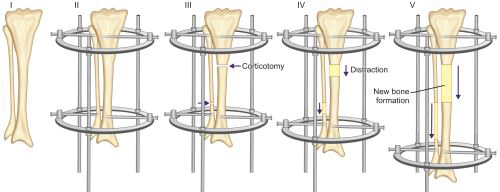

Russian surgeon, Gavriil Ilizarov pioneered the revolutionary technique of bone and soft-tissue regeneration based on distraction osteogenesis in 1960s.

Principle: It is based on the principle of distraction histogenesis which states that gradual distraction of bone at the rate of 1 mm/day, regenerates new bone at the distraction site. At the site of distraction, fibroblast-like cells become metabolically active and secrete collagen. Dormant mesenchymal cells at the site get converted into osteoblasts and secrete osteoid. Growth changes are also seen in soft tissues with cellular hypertrophy and hyperplasia in myocytes and capillary formation and30 development of nerves in direction of tension vector, so all tissues including bone are lengthened.

Assembly and technique (Figs. 1.39A and B): The Ilizarov external fixator is a special modified external fixator that has a complex assembly of metal rings, threaded rods, and Kirschner wires. Wires are passed through skin and soft tissue and drilled through both bony cortices. Wires are attached under tension to half and full metal rings encircling the bone. Assembly is completed by connecting the rings to threaded rods. Assembly can be angulated using hinges if deformity correction is planned. After fixation of the assembly, corticotomy (cutting the cortices of bone while leaving a posterior hinge of periosteum intact for vascular supply) is done in the bone to be lengthened. Corticotomy is usually done at metaphysis because of high potential for osteogenesis in metaphyseal cancellous bone. Gradual distraction is started after few days of corticotomy. Few days are given as a latency period for hematoma to form and organize at site of corticotomy. Rate of distraction is kept slow at 1 mm/day at a rhythm of 0.25 mm every 6 hours. New bone is formed by gradual distraction at the corticotomy site.

Uses of Ilizarov method are given in Box 1.10.